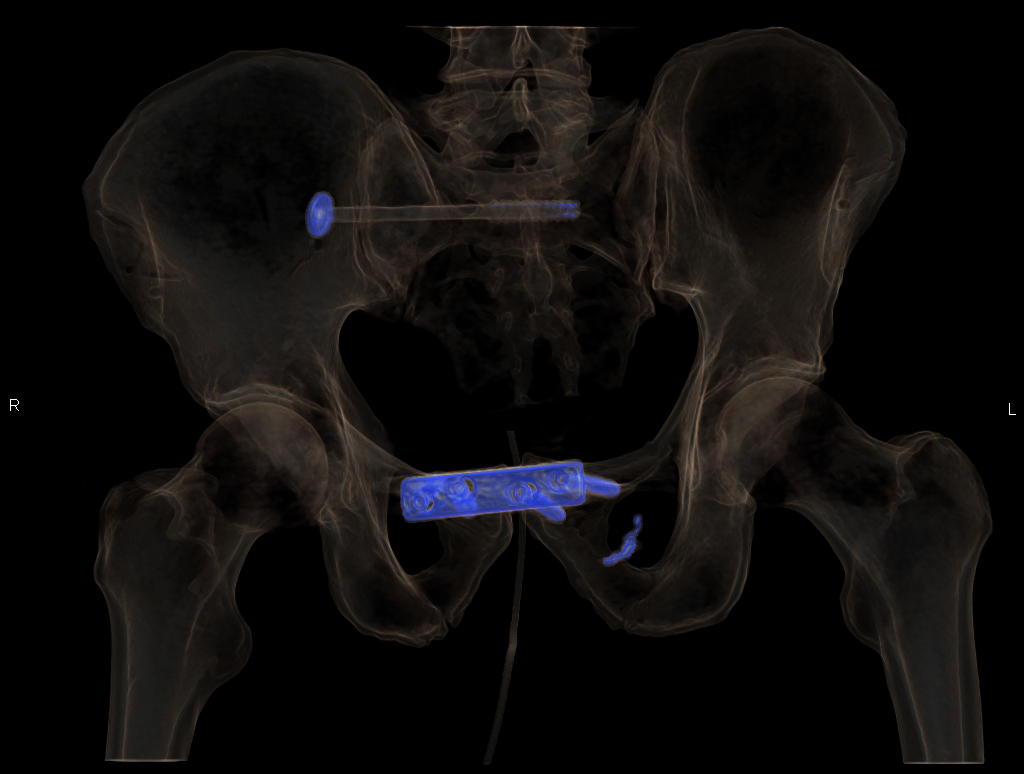

In einem späteren nativen Kontroll-CT nach erfolgter Osteosynthese der Beckenringfraktur sind neben der Schrauben- und Plattenosteosynthese die metallenen Coils gut erkennbar (Abb. 5 und 6).

Abb. 5 Kontrolle im CT mit sichtbaren Coils

Abb. 6 Kontrolle der Osteosynthese mit sichtbaren Coils links